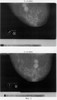

Пример 4. Сенерина С.В., 1931 года рождения. Диагноз: Tumor правой молочной железы (два узла) 5.05.2004 (снимок прилагается – фиг.1), диагноз поставлен рентгенологически, подвержен на УЗИ. От назначенной химиотерапии и лучевой терапии отказалась, принимала тамоксифен. Прошла 105-дневный курс предложенной фитотерапии. На контрольных рентгеновских снимках (фиг.2) от 21.10.2004 наблюдается уменьшение опухолевых узлов в 1,5-2 раза. Субъективные ощущения пациентки позволяют говорить о положительной динамики состояния (на фиг.1 – снимки до лечения, на фиг.2 – после лечения – в 2 ракурсах).